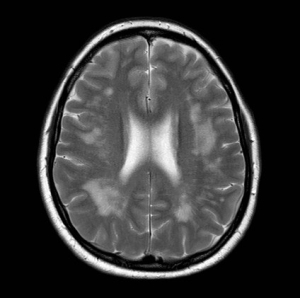

一名麩質(zhì)腦病患者的腦部MR成像顯示白質(zhì)信號過度改變。這類患者通常表現(xiàn)為頑固性頭痛。無麩質(zhì)飲食可消除頭痛并阻止白質(zhì)變化的進展。如果不治療,這些患者可能最終會患上血管性癡呆。